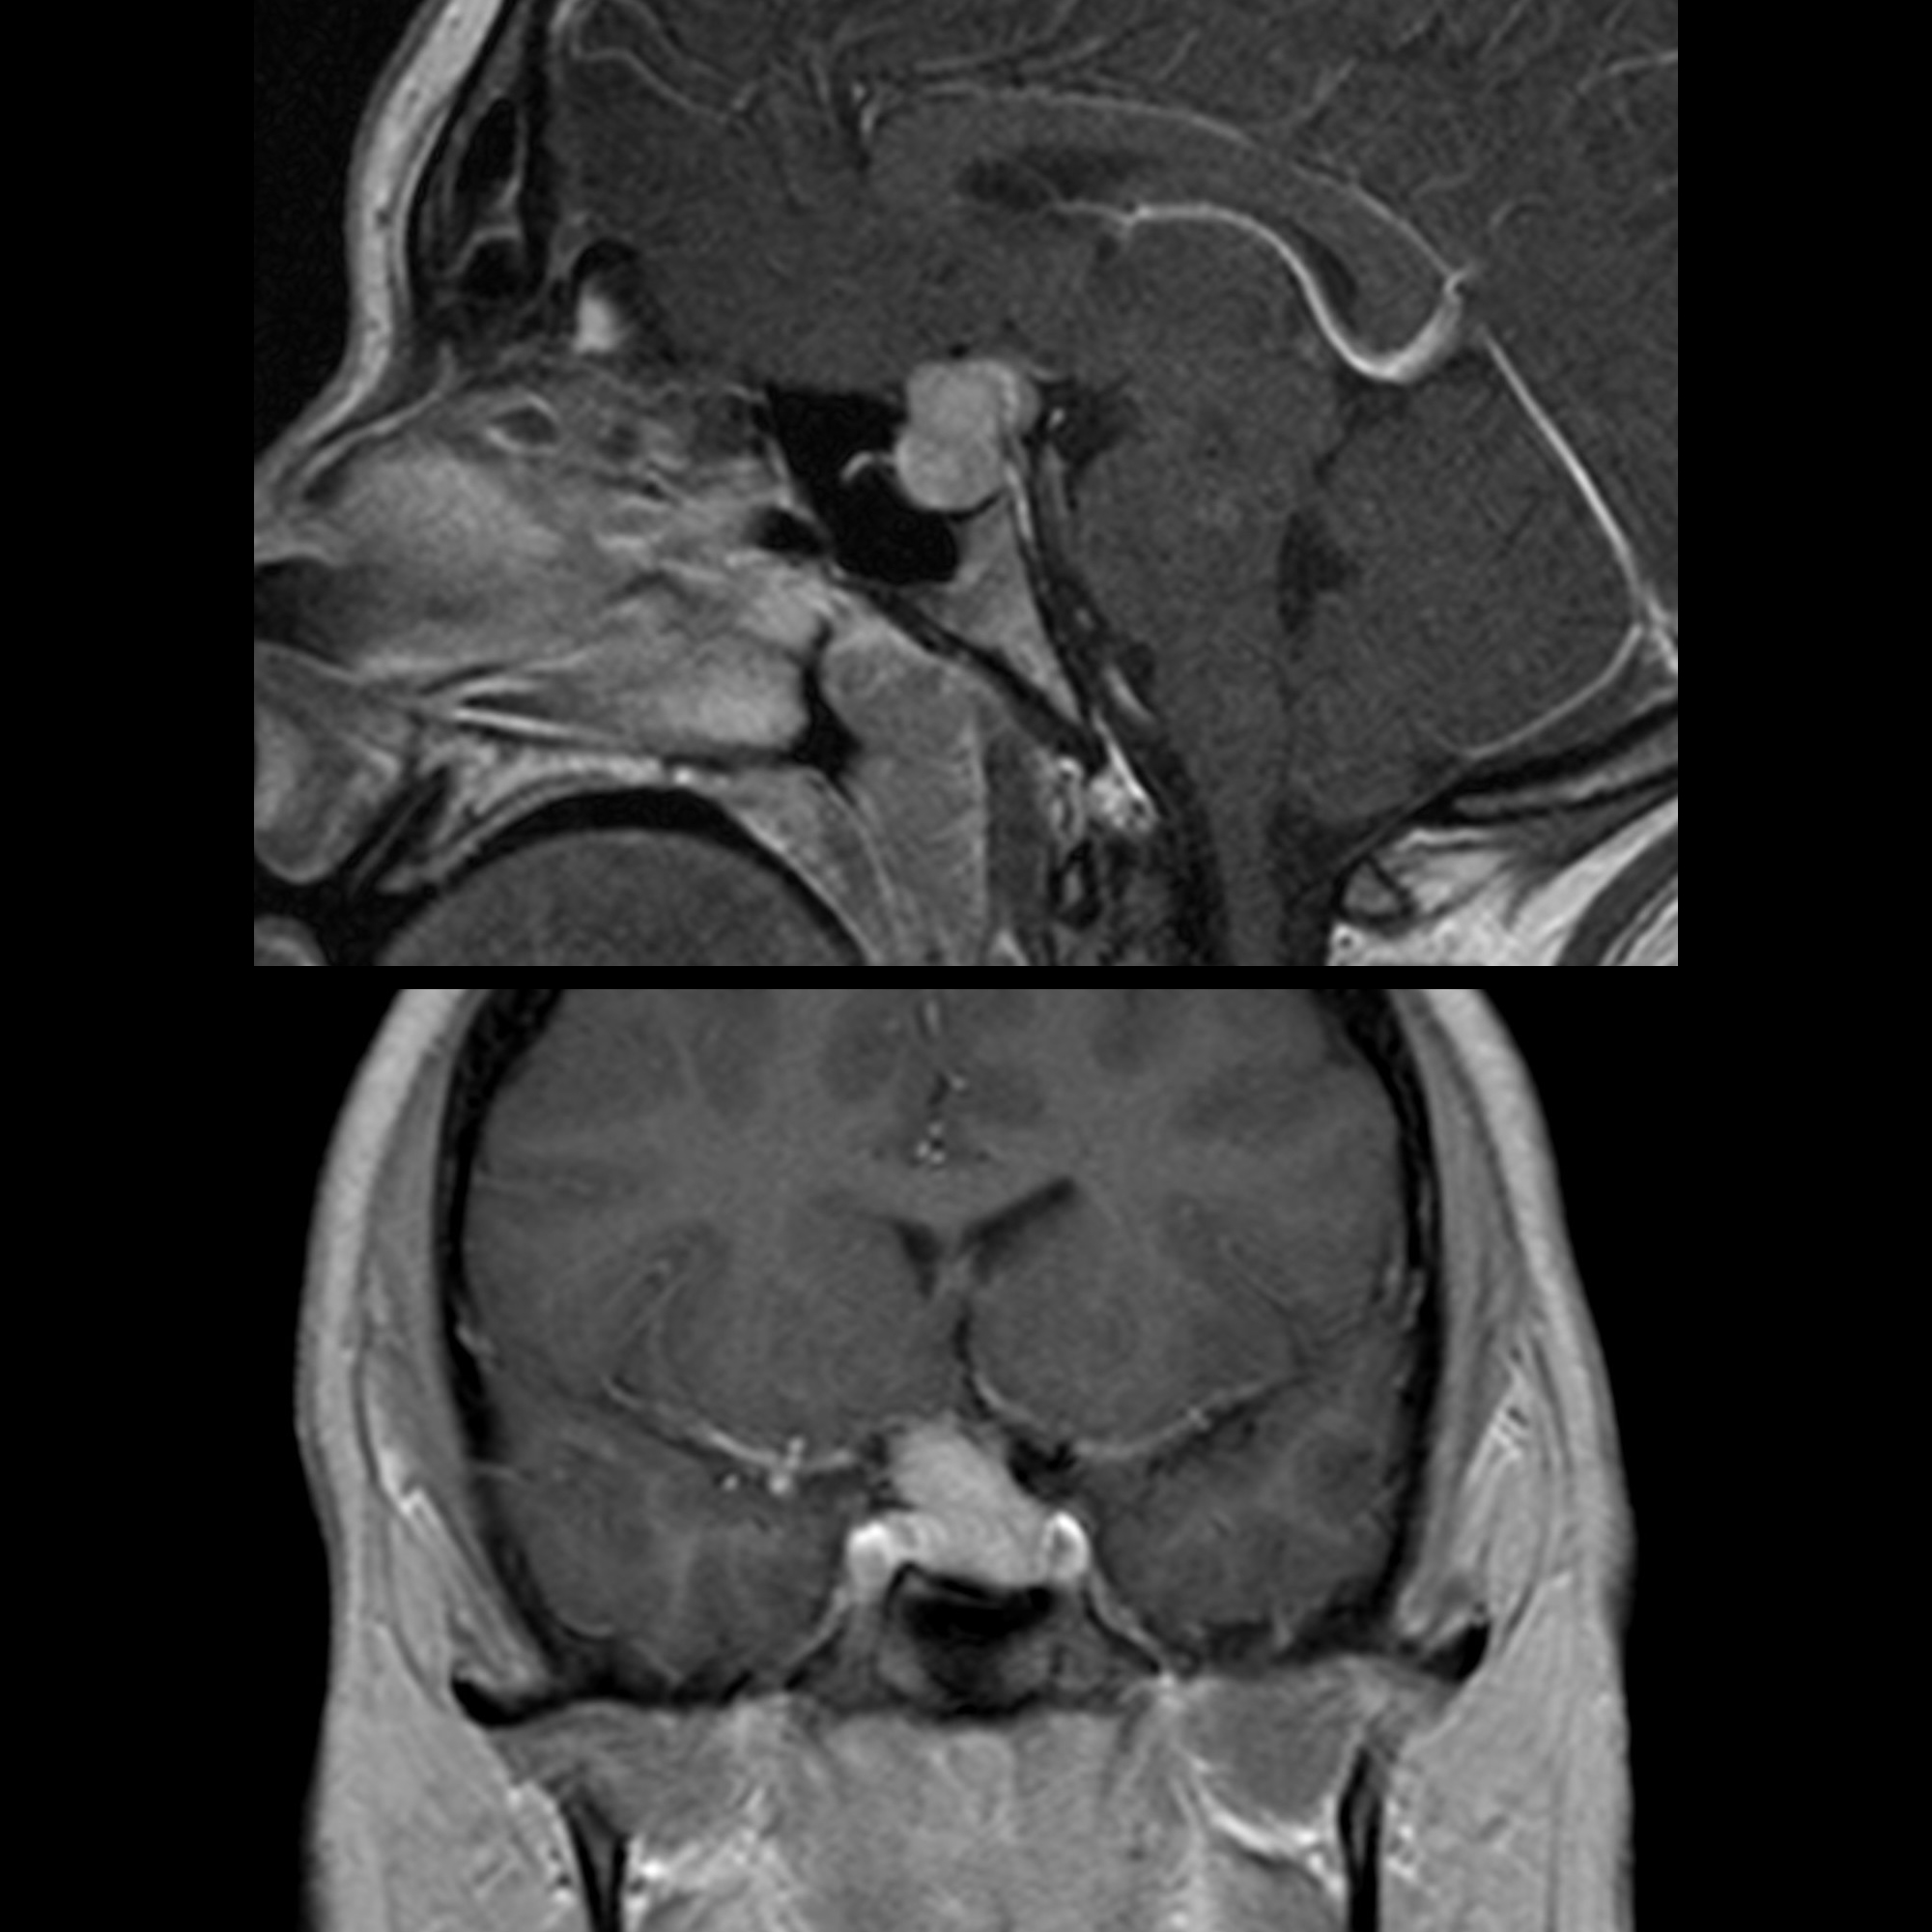

Understand the anatomy and clinical significance of the pituitary with infundibular stalk. This guide explores the structure, function, and common pathologies affecting the pituitary gland and its connection to the hypothalamus. Learn how these critical components regulate hormone production and why imaging the infundibulum is essential for diagnosing endocrine disorders and neurological conditions.